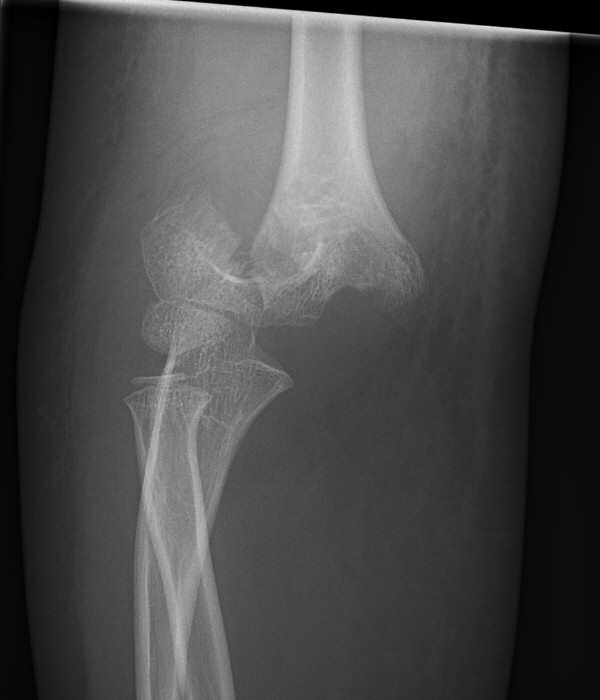

Suprakondylär humerusfraktur, Gartland 1.2, Rogers line delar capitulum radii, behandlades icke-kirurgiskt